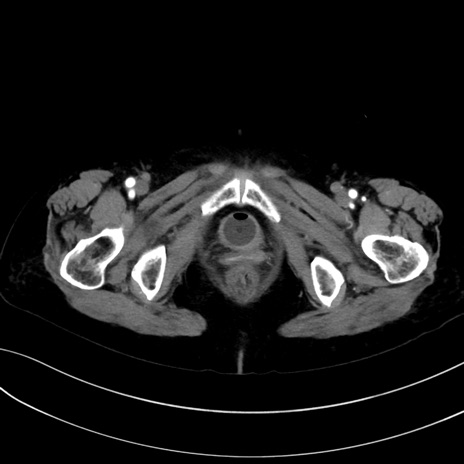

症例13 CT(横断像)1日半後